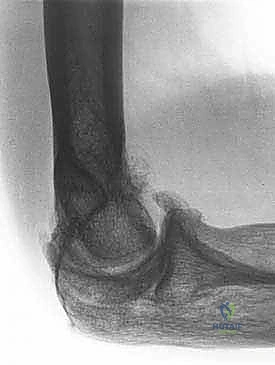

- الأشعة السينية (X-rays): لتقييم شكل العظام، البحث عن الكسور القديمة، وتحديد أماكن النتوءات العظمية والأجسام الحرة الكبيرة.

- الأشعة المقطعية ثلاثية الأبعاد (3D CT Scan): وهي الأهم قبل الجراحة. تعطي الجراح خريطة مجسمة دقيقة لكل نتوء عظمي وكل حاجز ميكانيكي داخل المفصل، مما يسهل استهدافه بالمنظار.